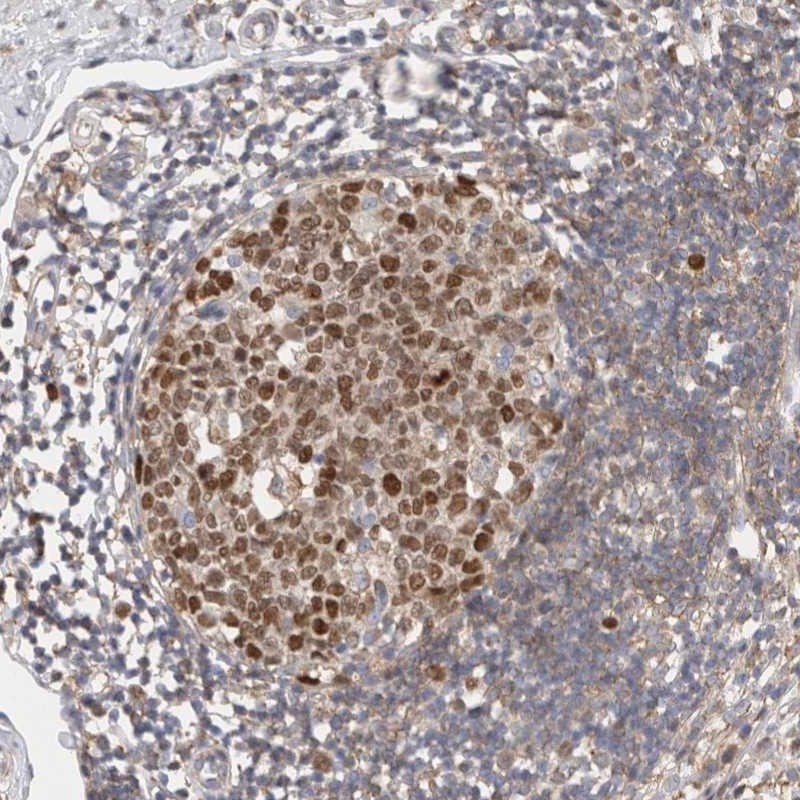

Immunohistochemical staining of human appendix shows strong nuclear positivity in lymphoid reaction center cells.